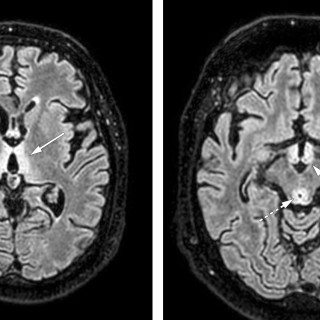

CT-bildene er fra en undersøkelse med opptak uten intravenøs kontrast. Bildet til venstre viser høy attenuasjon i myokard i venstre ventrikkel, og i mindre grad i høyre ventrikkel. Attenuasjonen er tilnærmet lik skjelett i bildet, og tettheten kan passe med forkalkninger. Opptaket er gjort på en spektral-CT, som har økt mulighet for å differensiere mellom ulike vevstyper. Maskinen utnytter de ulike energinivåene i røntgenstrålen, og den kan skille mellom grunnstoffer som jod og kalk utfra absorpsjonsnivået, da begge gir høy attenuasjon. Kalksuppresjon, vist på bildet til høyre (B), bekrefter...